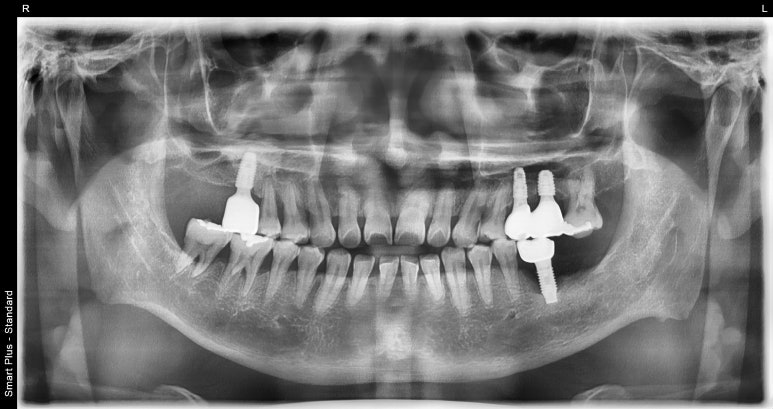

임플란트 1차 수술 후

2022-09-16

발치 4개월 후 임플란트 1차 수술을 진행해 픽스처를 식립했습니다.

이렇게 임플란트 수술을 마치고 환자분 잇몸 상태를 고려해 지속적인 잇몸치료도 권유 드렸습니다.

이제 잇몸뼈와 임플란트가 잘 유착되었는지 확인 후 수치가 잘 나왔다면

치아 역할을 하는 크라운 본을 뜨고 크라운을 제작해 얹어주는 작업만 남았는데요.